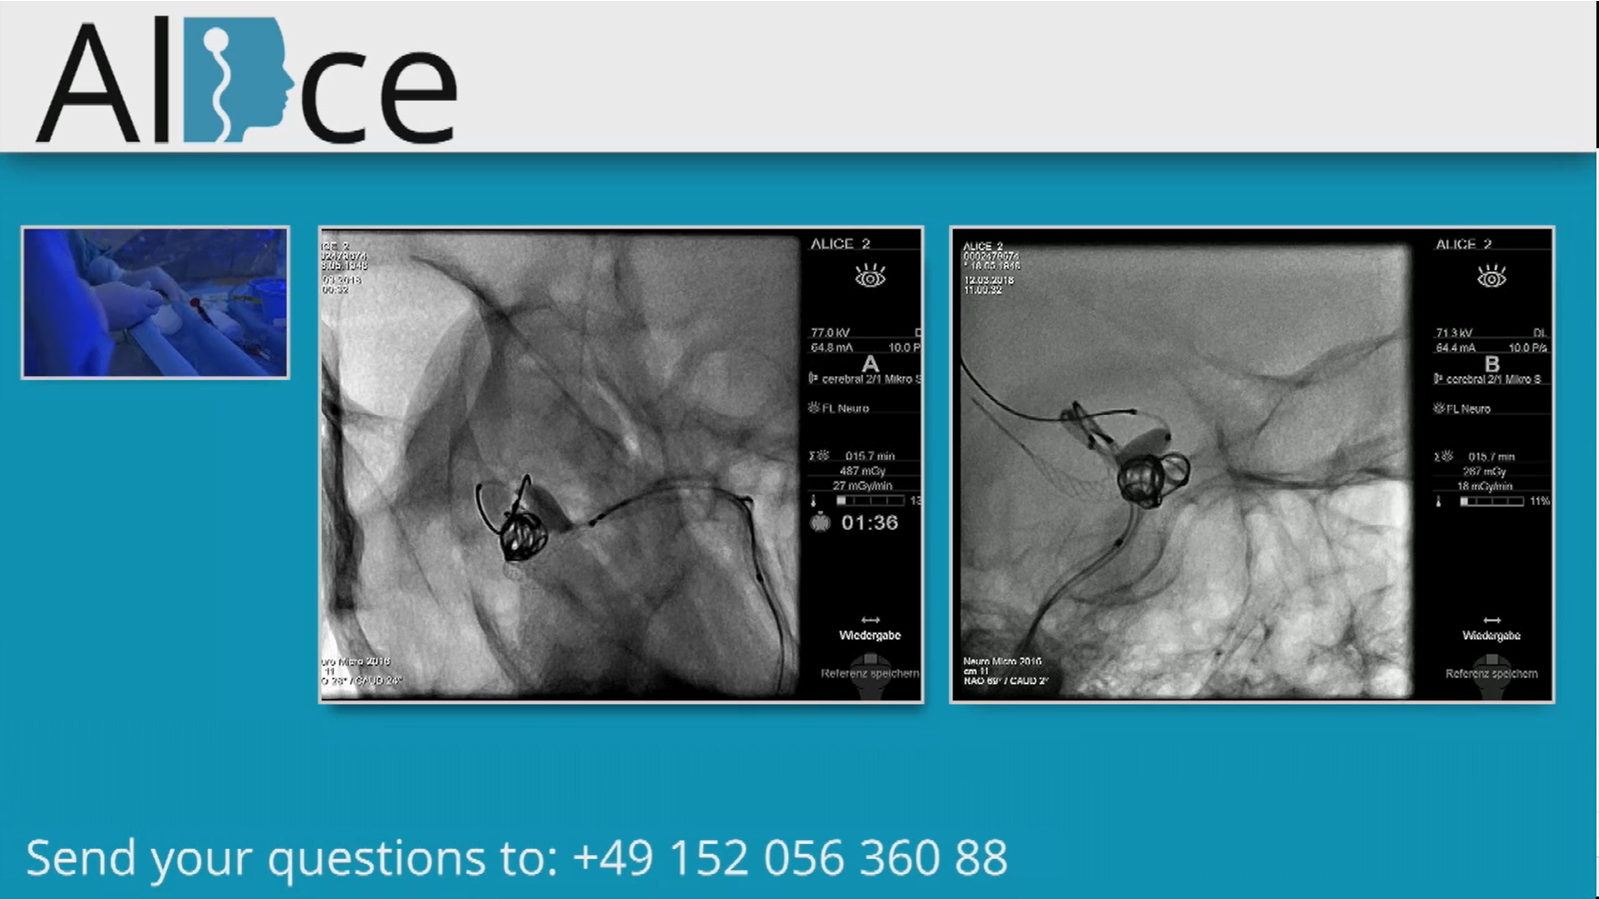

Small basilar tip aneurysm treated by kissing balloons and coils and followed by V stenting

Left MCA aneurysm treated by kissing balloons and coils and followed by T stenting